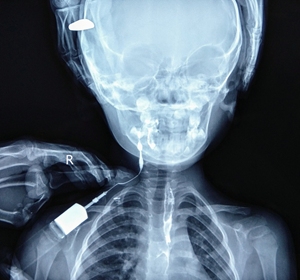

A contrast study was done by injecting iodinated contrast medium through the external opening, which revealed an irregular tract with beaded appearance on right side of neck extending cranially into the right lateral wall of oropharynx. Esophagus and stomach too showed the swallowed contrast, confirming the diagnosis of complete second arch branchial fistula.

Branchial apparatus consists of 5 mesodermal arches separated by invaginations of the ectoderm called as clefts. Anomalies of the branchial apparatus include branchial cysts, sinuses and fistulas.1,2 Branchial anomalies are common congenital lesions of the neck, of which second branchial complex anomalies are most common, accounting for about 95% of these lesions. A complete branchial fistula with 2 openings is rare.3 Branchial cysts are thought to occur due to entrapped remnants of branchial cleft or sinuses; branchial sinuses from entrapped remnants of cleft of pouches; and branchial fistulae occur from persistence of both pouch and cleft.4 The fistulous tract in second branchial fistula extends deep to the platysma, along the carotid sheath, and passes between carotid arteries bifurcation. Cranially, opening of the tract lies in the lateral wall of oropharynx at the region of tonsillar fossa.4 Second arch branchial fistula can be unilateral or bilateral. In case of unilateral, the right side preponderance is described.5 Fistulography and computed tomography (CT) fistulogram are the modality of choice for radiological diagnosis of second branchial arch fistula (Figure 1).1,3,5

Fistulography (performed with opacifying the fistula with contrast media) delineates the fistulous tract extending from the external cutaneous opening at the lateral neck to the tonsillar fossa.1,2 CT fistulogram with reformatted images demonstrates the fistulous tract as well as its relationship with important structures of the neck.1 Ultrasound and magnetic resonance imaging (MRI) has less diagnostic value in the diagnosis of fistulous tract, but more advantageous in the diagnosis of branchial arch cysts.1,5 Second arch branchial fistula are usually diagnosed in infancy or childhood with patient presenting with the complaints of watery or purulent discharge from an opening at the anterior aspect of lower third of the neck.3 The treatment of choice of second branchial arch fistula is complete surgical excision of the fistulous tract.1,2,4 Complete second arch branchial fistula is congenital anomaly of neck in the paediatric age group. The incidence of branchial fistula is less as compared to branchial cysts and sinuses. Fistulography (performed with opacifying the fistula with contrast media) is the best radiological diagnostic tool for pre-operative evaluation. Complete surgical excision is performed as the treatment of choice of second branchial arch fistula (Figure 2).